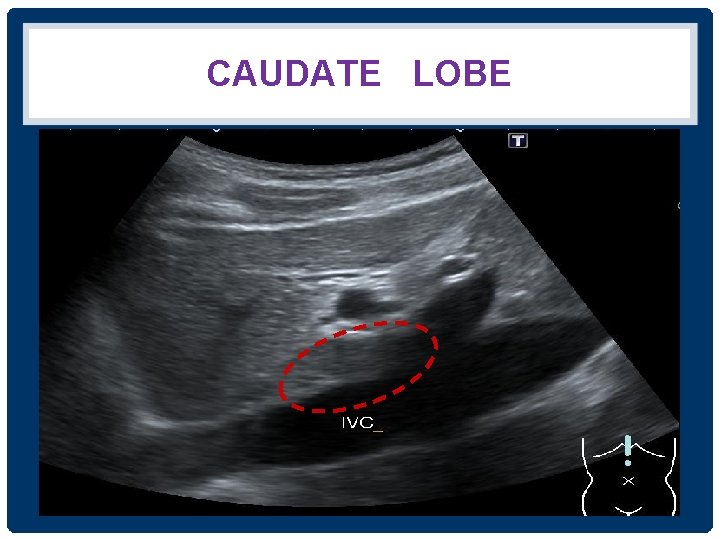

CAUDATE LOBE IVC